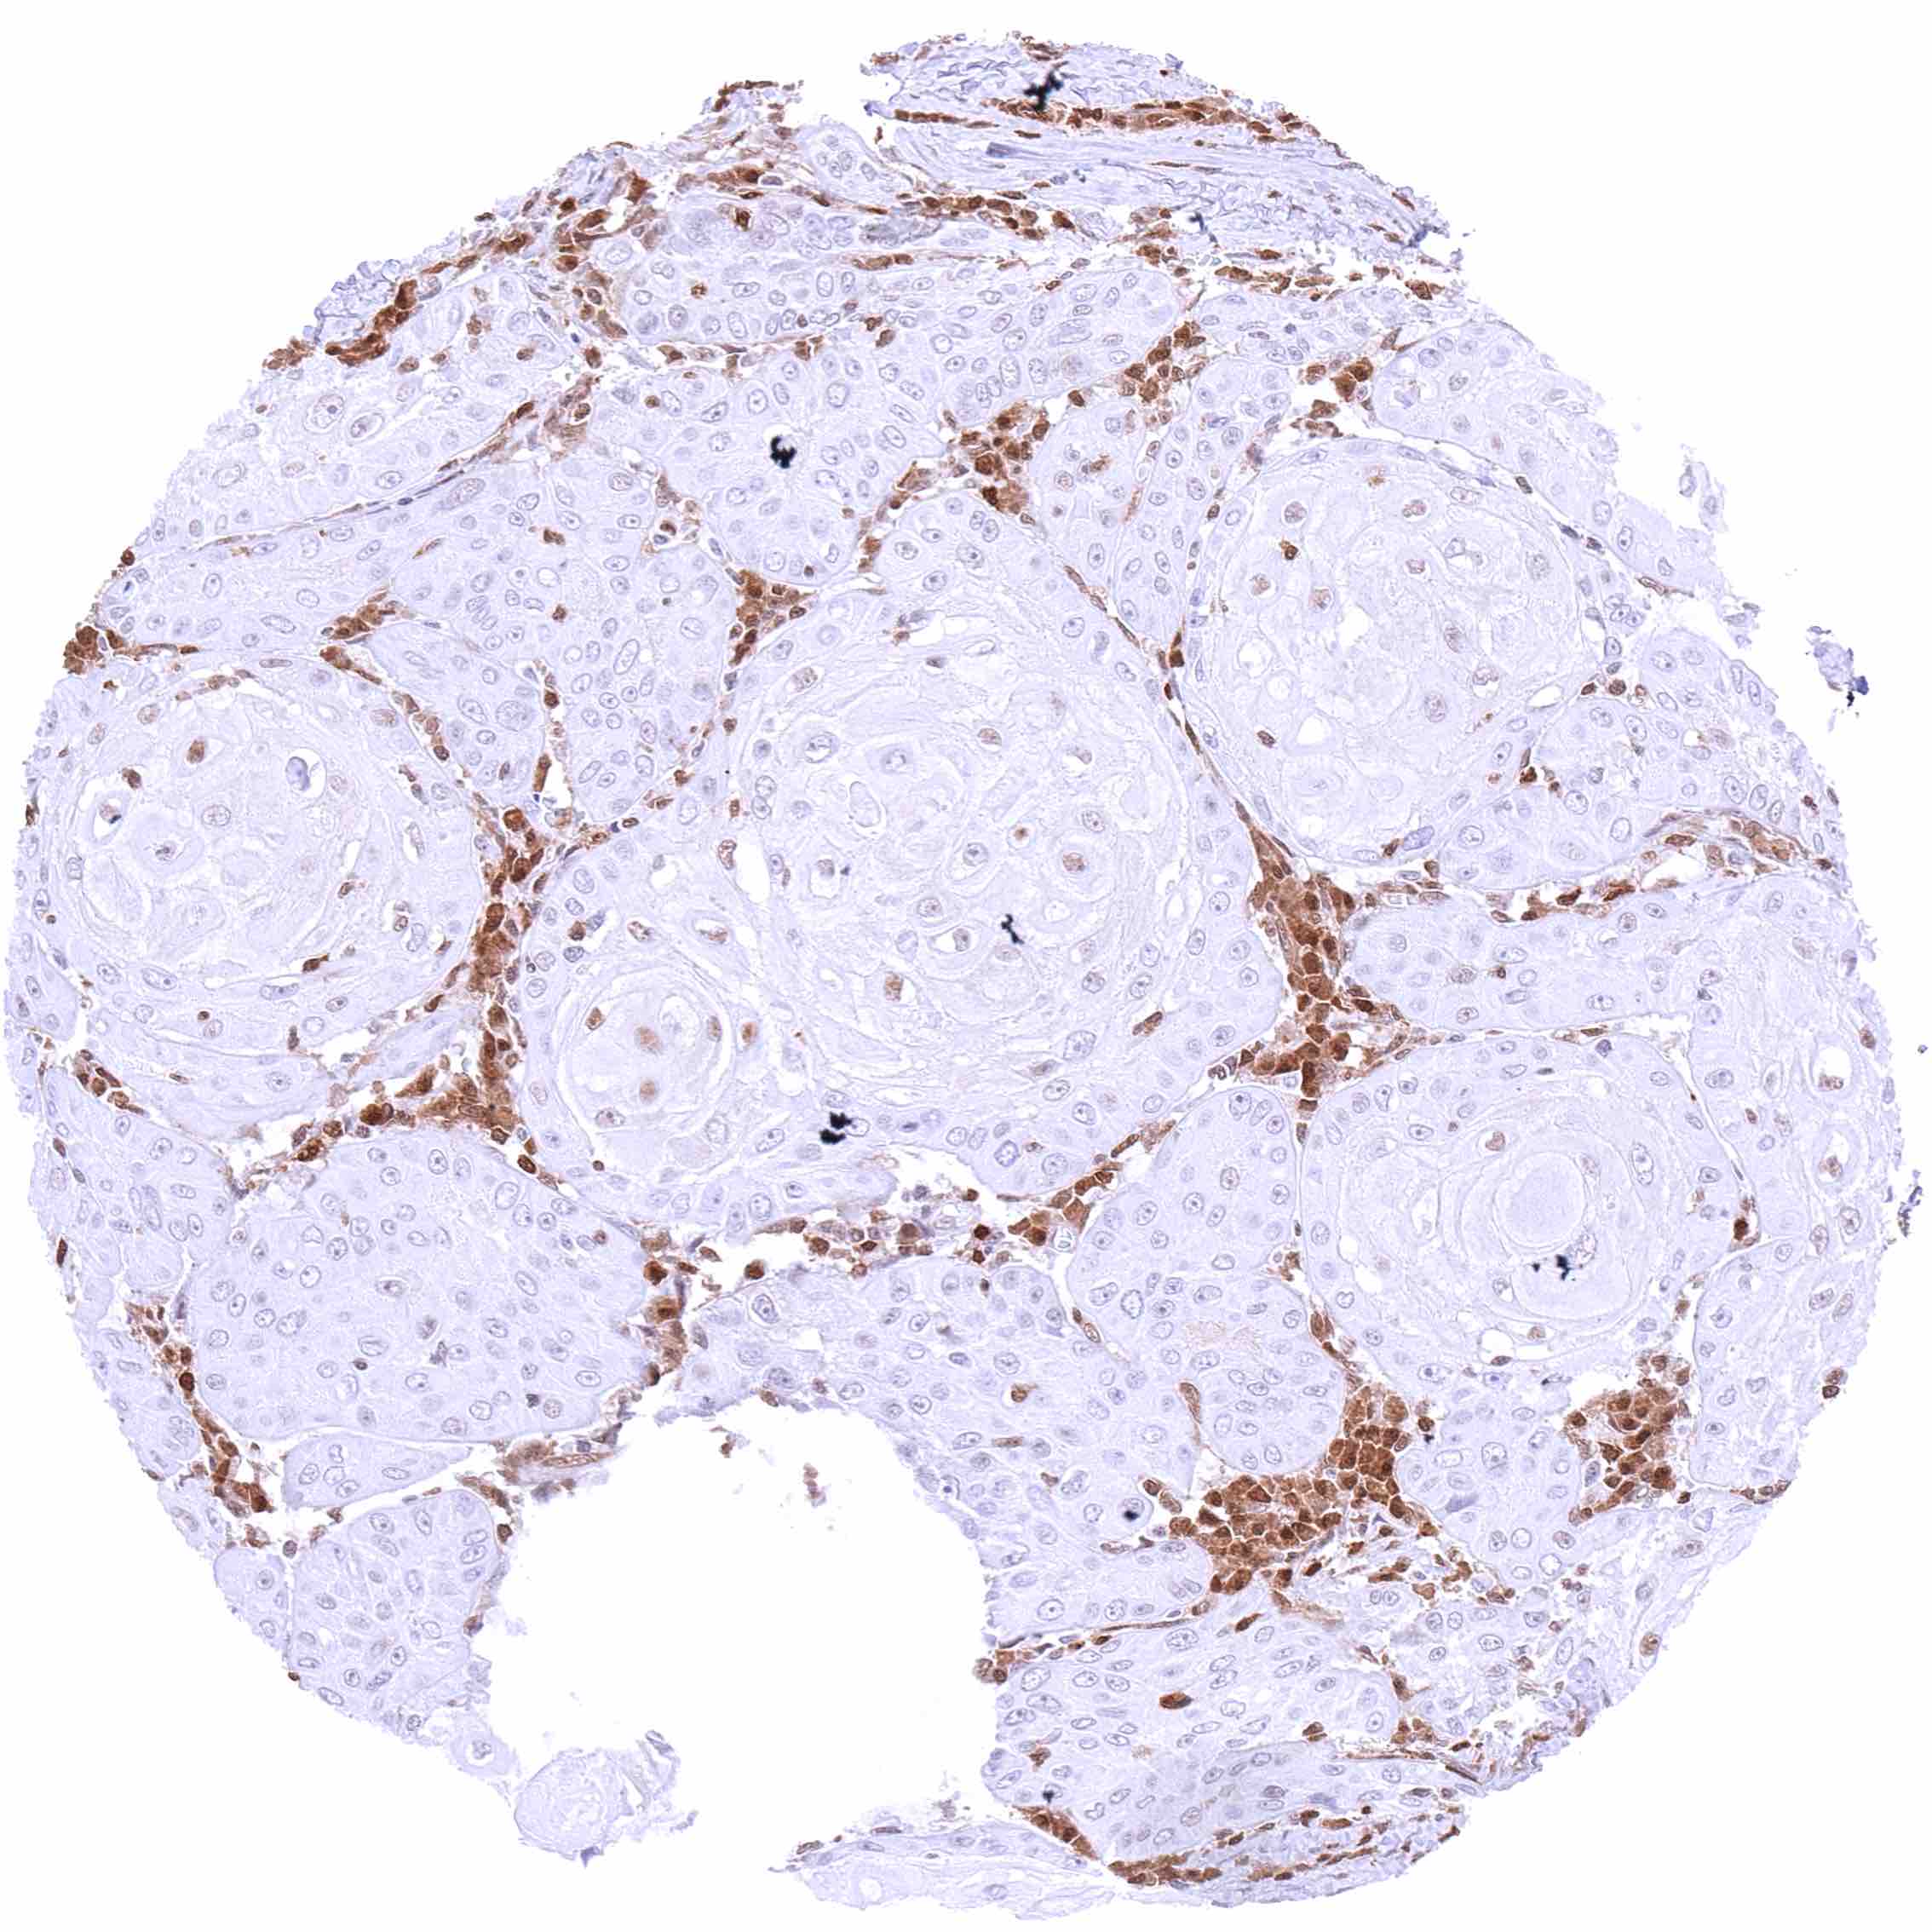

Penis – Squamous cell carcinoma with a variable, weak to strong, predominantly cytoplasmic p27 positivity of most tumor cells.